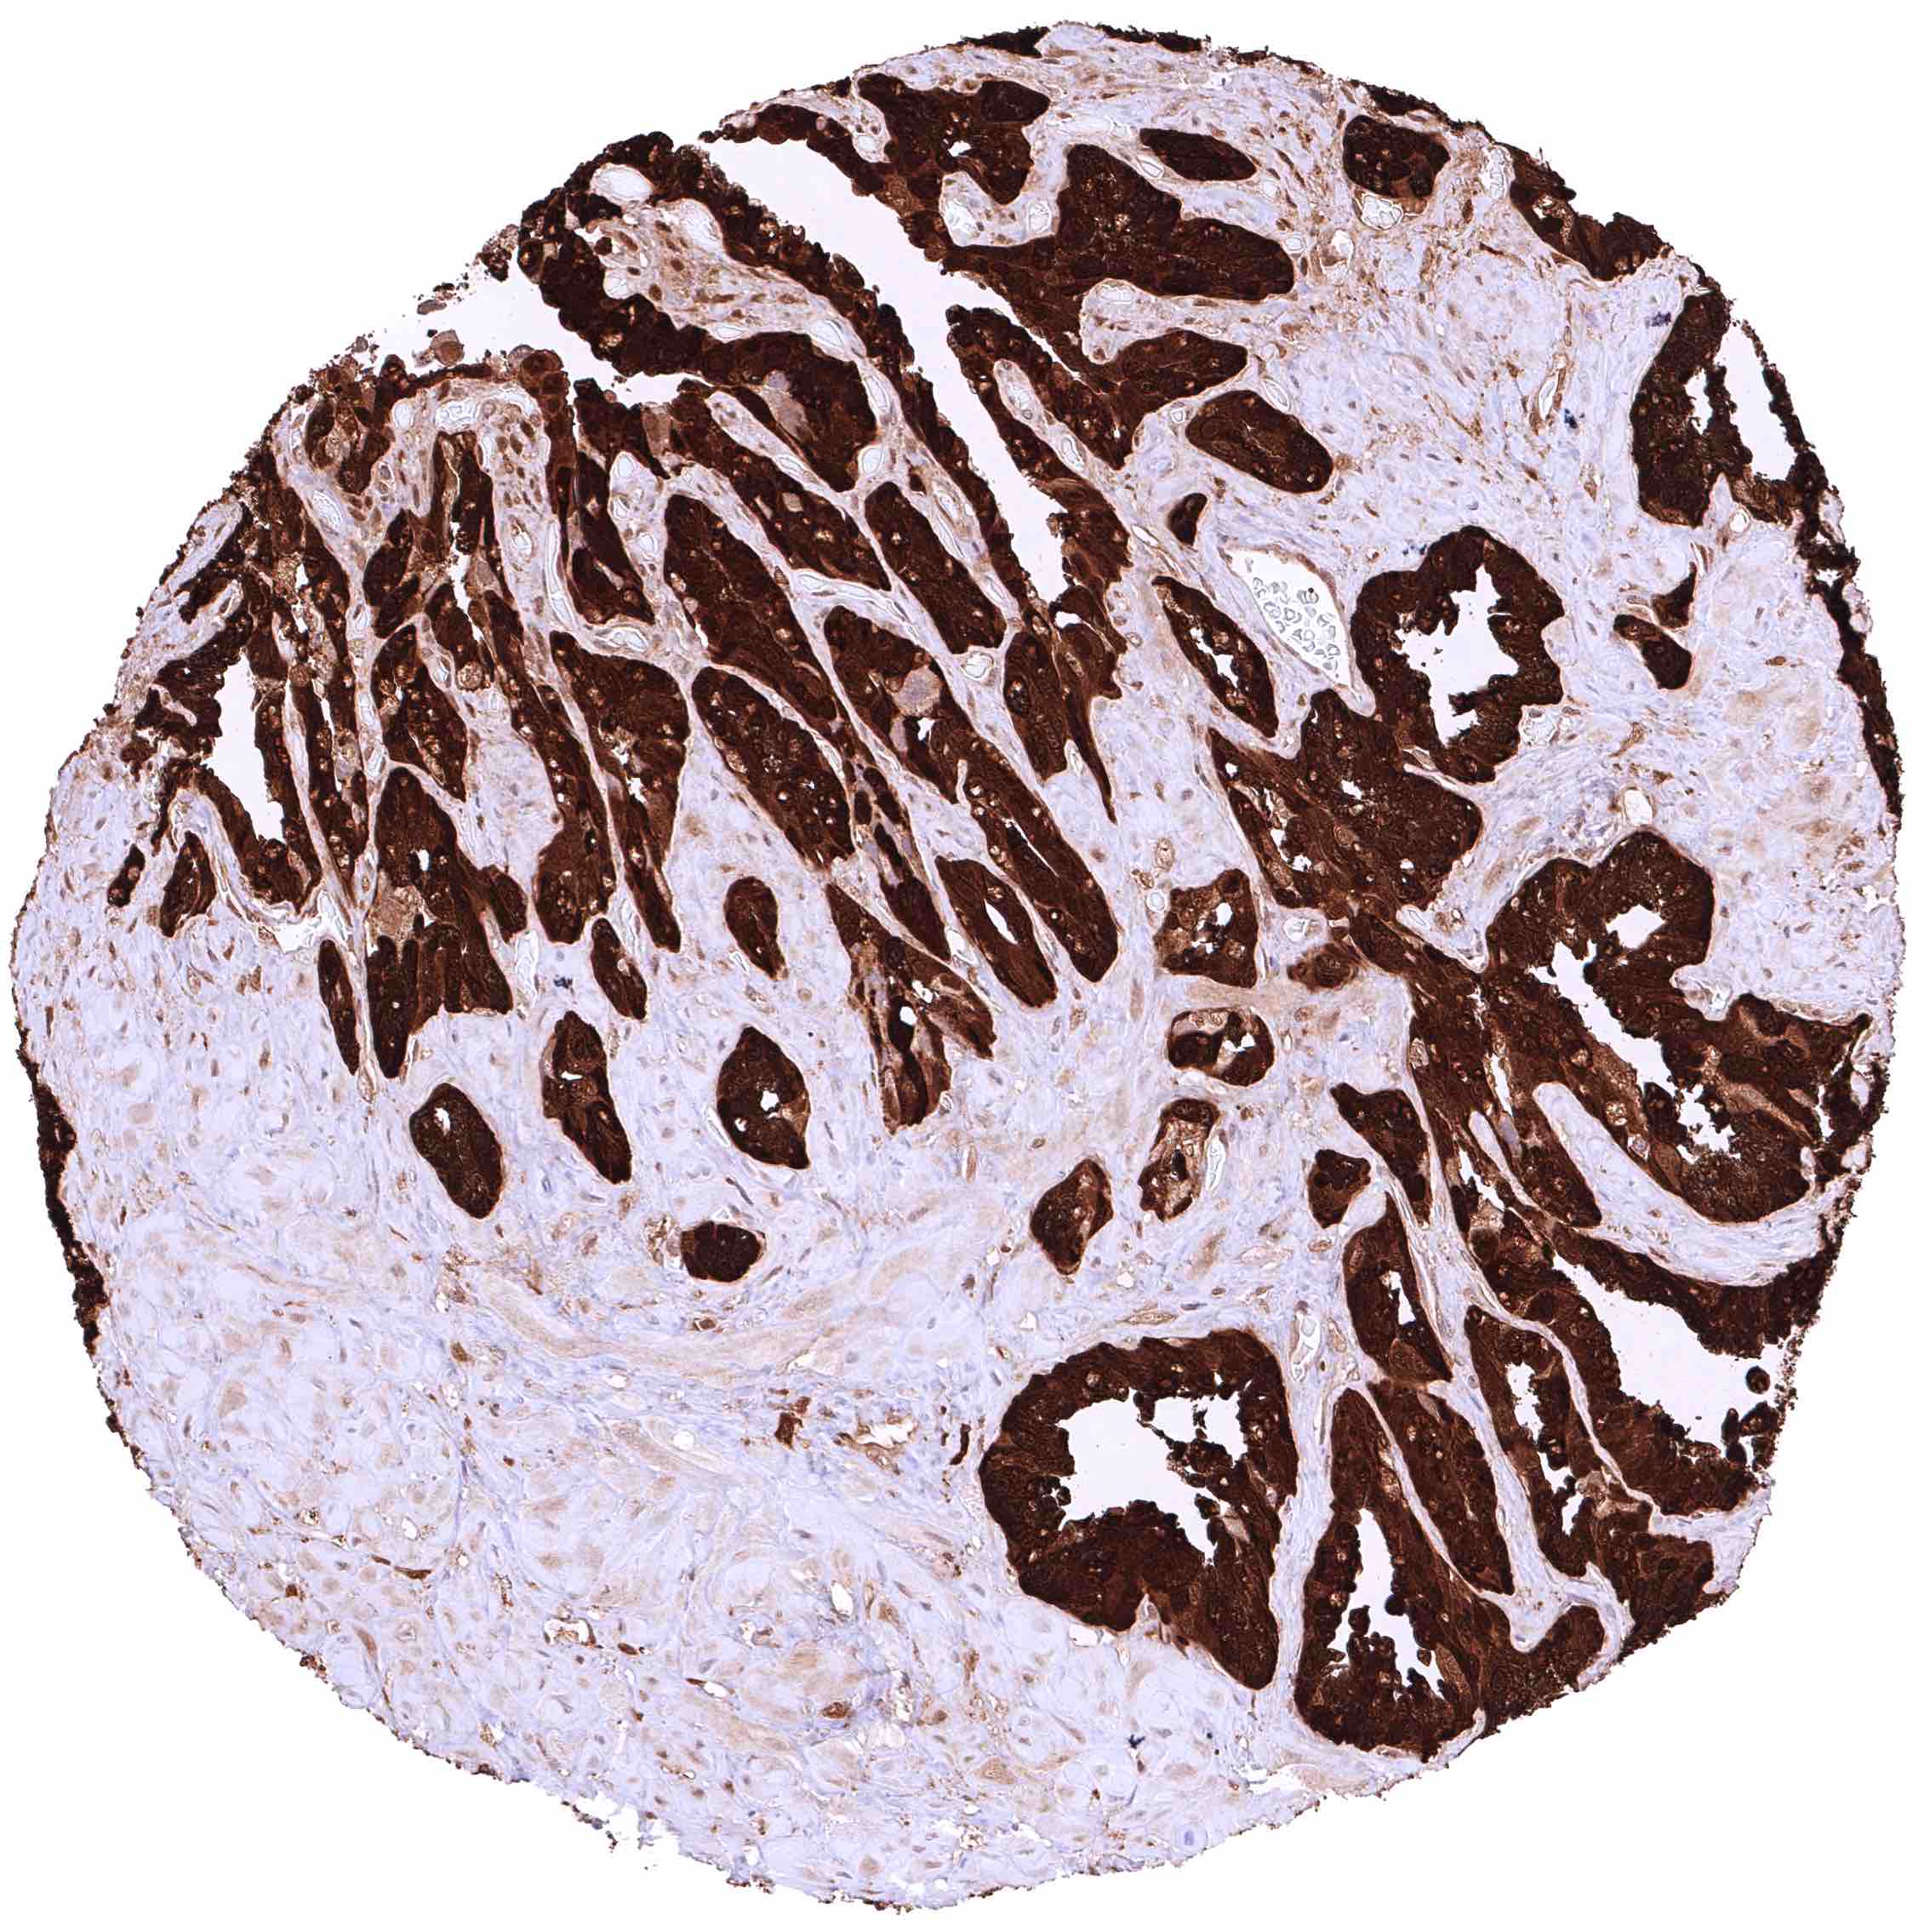

Prostate – Intense nuclear and cytoplasmic GSTP1 staining of basal cells while staining is faint or absent in acinar cells

Prostate – Intense nuclear and cytoplasmic GSTP1 staining of basal cells while staining is faint, weak or even absent in acinar cells